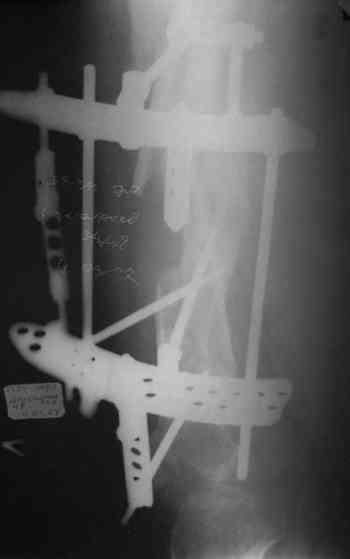

Лучше бы закрытый интрамедуллярный, конечно.

Надо делать чрескожную подвертельную остеотомию, чтобы получился открытый клин. Проблемы будут и с формированием канала, надо развертки типа наших. Был как-то похожий случай, сделали одномоментно, сняли аппарат 5-месячый на столе, заштифтовали с подвертельной остеотомией (в приложении).

Можно все коррекции сделать и в аппарате, и потом заштифтовать, тогда останется только одна проблема формирования канала.